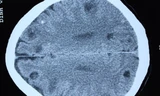

Ngoài ra, sán lá gan ký sinh trong đường mật, làm đường mật dày lên, xơ hóa, thoái hóa mỡ gan, cổ trướng với kích thước gan to gấp 2-3 lần bình thường. Bệnh còn gây sỏi mật, thậm chí là nguyên nhân quan trọng dẫn đến ung thư đường mật.